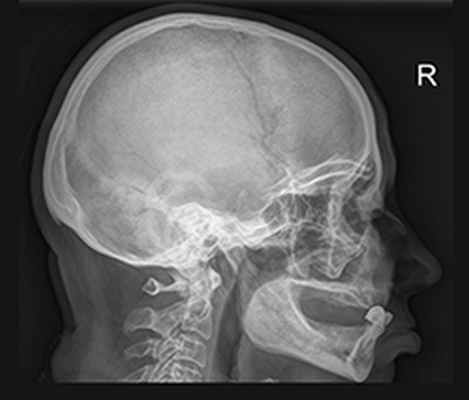

Рентгенография черепа

Рентген черепа – это метод лучевой диагностики, который применяется для исследования костей свода и основания черепа, костей лицевого скелета и головного мозга. Рентгенологическое исследование черепа помогает поставить диагноз, решить вопрос с выбором тактики лечения и проконтролировать динамику лечебного воздействия. Рентген черепа обычно выполняется в положении лежа или сидя с фиксированной с помощью специальных приспособлений головой. Врач может назначить исследование в одной или нескольких проекциях: правой боковой, левой боковой, переднезадней, заднепередней, аксиальной, полуаксиальной, прицельной. При этом потребуется снять все металлические аксессуары с шеи и головы.

Диагностика заболеваний черепа может включать различные виды рентгенографии, которые назначаются в зависимости от клинических проявлений и истории заболевания:

- обзорная рентгенография черепа;

- прицельная рентгенография:

- рентгенография сосцевидных отростков височной кости;

- рентгенография височно-нижнечелюстных суставов.

Обзорная рентгенография черепа проводится в обязательном порядке при травмах головы, с целью обнаружения переломов свода и основания черепа, смещения костных отломков. В случае высокой плотности костной ткани переломы могут быть не распознаны, поэтому рентгенологический метод уступает по точности и достоверности компьютерной томографии, но является более простым и быстрым способом диагностики.

Помимо переломов обзорный рентген черепа позволяет обнаружить: